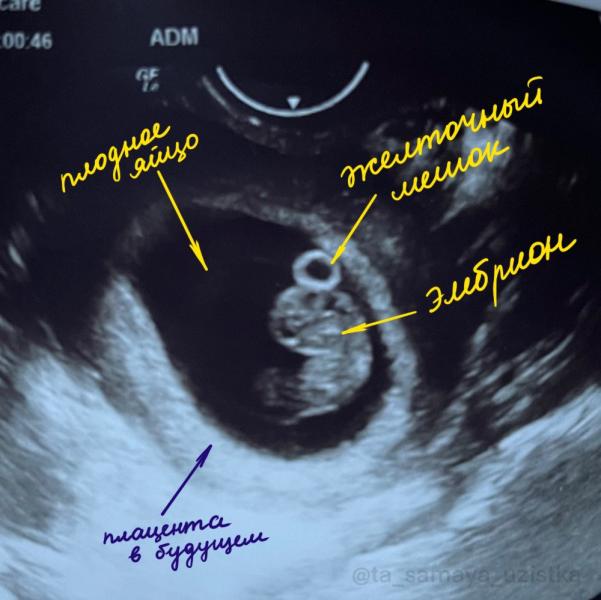

Что касается самого первого УЗИ (после появления заветной второй полоски на тесте при задержке менструации), плодное яйцо можно увидеть на сроке от 5 недель (от первого дня последней менструации при цикле 28 дней), при ХГЧ в крови более 1000 ММЕ/мл), желточный мешок начинает визуализироваться с 5,5 недель, эмбрион можно увидеть так же с 5-5,5 недель, тогда же начинает! биться сердечко. Всё это касается УЗИ через влагалище, при УЗИ через живот сроки смещаются на 3-7 дней позже. И помним про свой цикл, не у всех он 28 дней, как по книжке)

На фото: живой эмбрион на сроке 8 недель и 3 дня